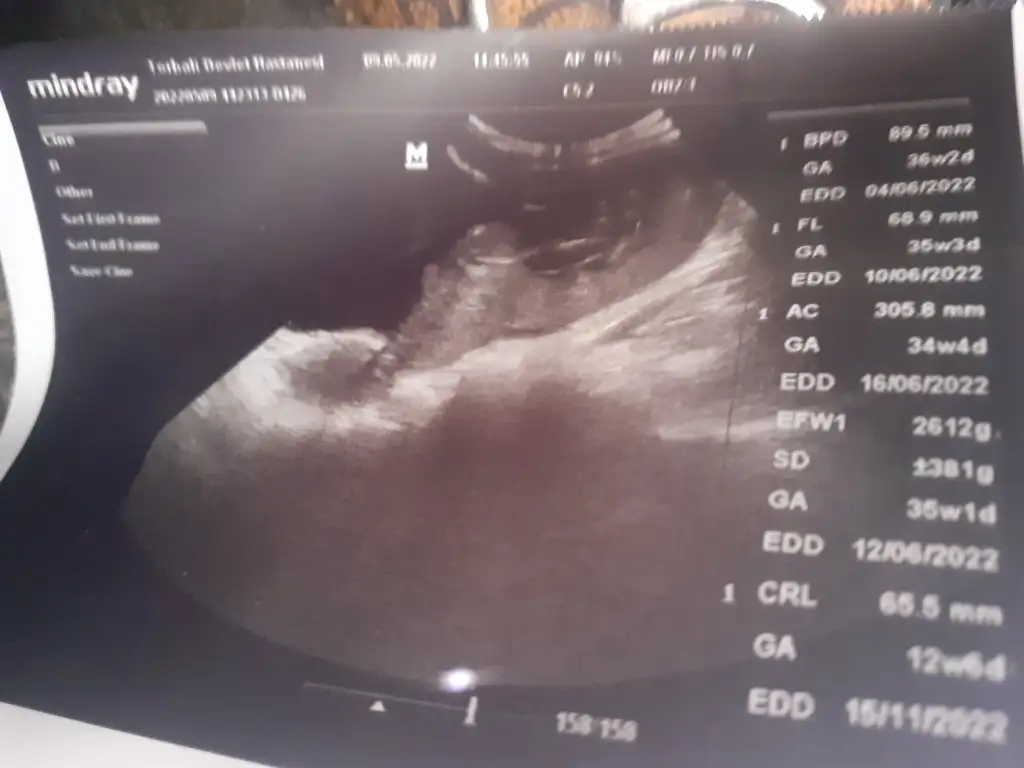

Mrb 12+6 tahmin alabilir miyim lutfen ikra meyra 🙏

Eklentiler

• IMG_20220510_114117.webp

IMG_20220510_114117.webp

14,7 KB · Görüntüleme: 98